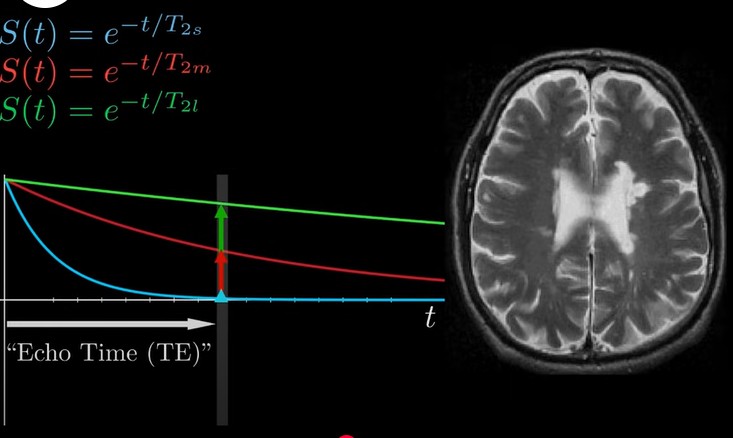

what is a T2 weighted image?

based on imaging using echo times, the voxel tells us how quickly the precessing spins in the voxel got out of phase with each other

bright if they dephase slowly

dark if they dephase quickly

<p>based on imaging using echo times, the voxel tells us how quickly the precessing spins in the voxel got out of phase with each other</p><p>bright if they dephase slowly</p><p>dark if they dephase quickly</p>

what is echo time?

how long you wait to detect signal once spins have been knocked out of alignment with field/excited

parameter chosen by MRI technician deliberately to maximise contrast between tissues of interest

at certain echo time, tissue has different signal strength, corresponding to different brightness of tissue

<p>how long you wait to detect signal once spins have been knocked out of alignment with field/excited</p><p>parameter chosen by MRI technician deliberately to maximise contrast between tissues of interest</p><p>at certain echo time, tissue has different signal strength, corresponding to different brightness of tissue</p>

how can we change TR and TE to alter T1 and T2 effect on image contrast?

A longer TR than T1 values of involved tissues reduces the effect of T1 on image contrast - for all tissues, longitudinal magnetisation will recover almost fully between repetitions

A much shorter TE than T2 values of tissues involved reduces effect of T2 on image contrast - little time for T2 relaxation to affect strength of recorded echo